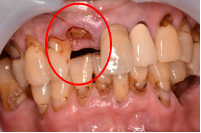

男性Mさん 50代(オールセラミック冠)

主訴

右上奥歯が、冷たいものにしみる。

治療内容

歯髄(神経および血管)まで到達する大きな虫歯でしたので、抜髄(歯髄を取り除く)をし、ファイバーコアをいれ、オールセラミック冠を被せました。

所感

現在、保険治療において、限定的ではありますが、大臼歯にも白い被せ物(プラスチック冠)ができるようになりました。しかし、実感としてプラスチック冠は、

- すり減りやすい。割れることがある。

- バイオフィルム(細菌およびそれから産生される副産物の塊)が付着しやすいので、歯周病および2次カリエス(被せ物と自分の歯の境目から再度虫歯になる)になるリスクが高い。

- 変色する。

という点を感じます。白い被せ物が保険の治療でできるという理由で、安易にプラスチック冠を選択し、割れたりすり減ったり、変色したらもう一度被せなおせばいいと考えるのであれば、一度立ち止まって考えてみてください。歯の量は、治療するたびに薄く少なくなり、歯根破折のリスクが高まります。もし大きな虫歯になってしまったら、最高レベルの根管治療をし、最良の被せ物であるオールセラミック冠を被せ、定期的にお口の中のクリーニングをし、同じ歯を2度と治療しないことが、歯を長持ちさせる最良の方法だと考えます。

オールセラミック冠(失活歯):¥104,500(税込)

Before

劣化したプラスチック冠

After